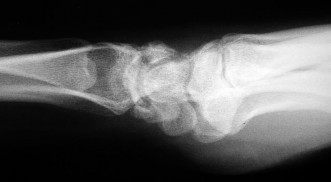

- الأشعة السينية (X-rays): هي الخطوة الأولى في تقييم الكسور، الخلوع، وتغيرات التهاب المفاصل. تساعد في تحديد مدى تدهور العظام والمسافات المفصلية. على سبيل المثال، تُظهر صور الأشعة السينية كسور السلاميات

أو كسور قاعدة العظم المشطي الخامس

، بالإضافة إلى علامات مثل "الدمعة الشعاعية" (Radiographic Teardrop) في الرسغ التي تمثل الزاوية الزندية الراحية الحرجة للكعبرة البعيدة

. - الأشعة المقطعية (CT Scan): توفر صوراً تفصيلية ثلاثية الأبعاد للعظام، وهي مفيدة جداً لتقييم الكسور المعقدة، مثل كسور العظم الخطافي (Hamate Hook Fracture) التي قد لا تظهر في الأشعة السينية العادية